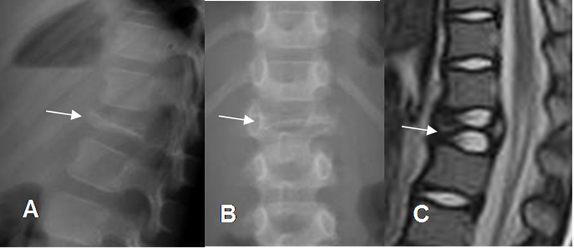

Fig 133. Granuloma eosinófilo.

A: Rx lateral, B: Rx AP, C: RM sagital en T2. Vértebra plana en L1, por granuloma eosinófilo.